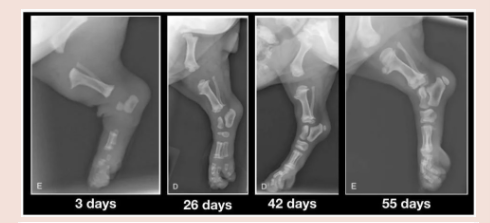

De groeiplaten van pups zijn nog niet verhard waardoor de beenderen bijna letterlijk zweven (zie foto's bij artikel). Daardoor zijn ze flexibel, maar ook heel vatbaar voor het ontwikkelen van problemen aan de gewrichten als we dus overdreven lang wandelen.

Eens de groeischijven dicht zijn, kan je hond stevigere wandelingen aan.